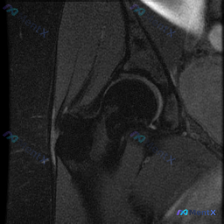

这是一张髋关节冠状位T1加权MRI,我们先梳理所有可见的异常:

- 股骨头区域:股骨头轮廓完整,关节间隙尚存,没有明显严重塌陷;但在股骨头前上方承重区,可见清晰的线样/带状低信号影,边界清楚,符合股骨头缺血性坏死典型的"双线征"内侧低信号带表现,其余骨髓信号基本均匀。

- 大转子区域:大转子外侧、股骨头颈交界外侧,有一团边界模糊的显著低信号占位性病变,已经侵犯到周围肌肉附着点,周围软组织界面也有改变。

最初有人只描述了"软组织积液",但这个影像表现其实和单纯积液差别很大,这点后面会说。

看到股骨头的带状低信号,第一反应肯定是股骨头缺血性坏死,这个征象太典型了:T1WI上坏死区因为纤维增生和骨质修复呈现低信号,双线征是早中期ONFH的特征性表现,目前关节没有塌陷,应该属于早中期病变。

但看到大转子的病灶后,就不能只停在这了。